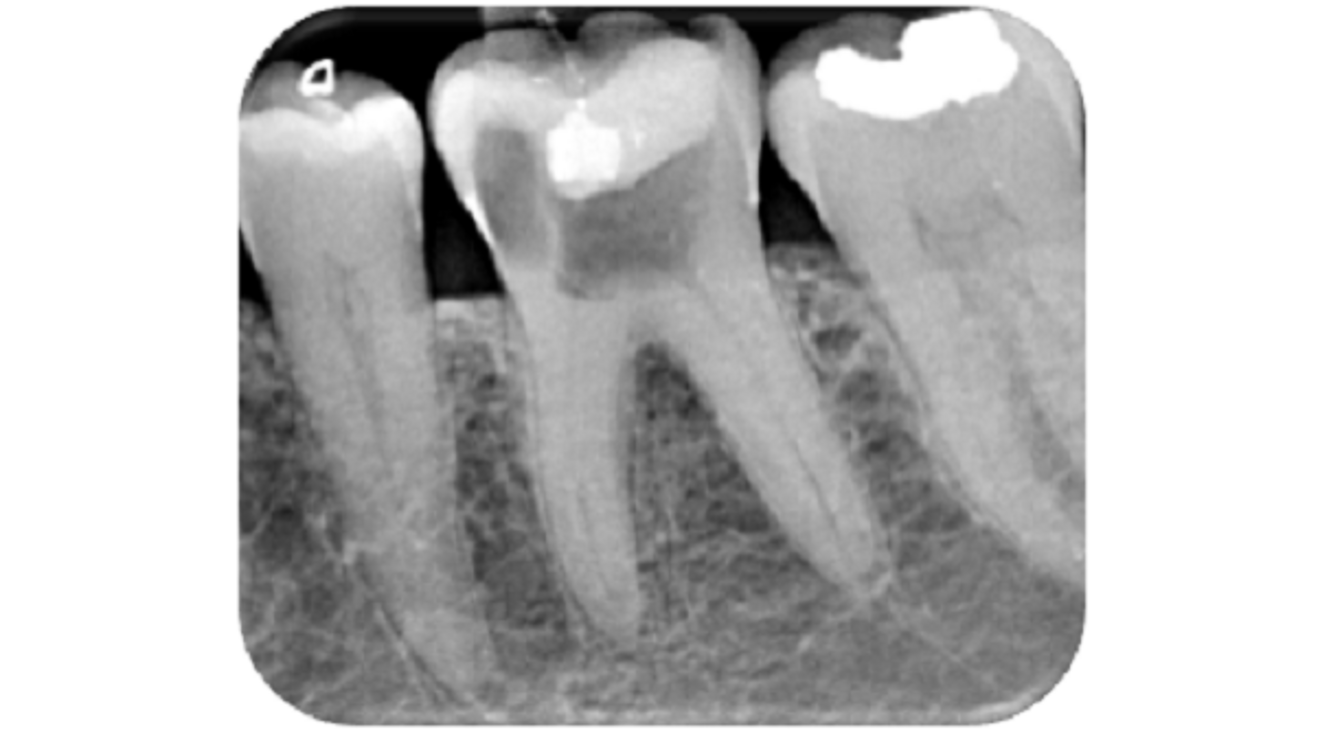

Fig. 16: Post-op radiograph showing the well-condensed obturation to within 2 mm of the radiographic apex and an adequate coronal seal provided by the composite restoration.

The patient was advised to take analgesics to relieve any discomfort and to expect some pain and possible tenderness of the tooth. Again, she was also advised about the possibility of an acute flare-up and/or swelling in the area, and the possibility of tenderness from the temporomandibular joint. If any of these scenarios occurred, she was to use anti-inflammatories and cold compresses and contact the dental practice. A master point long-cone periapical radiograph was taken for postoperative assessment of the endodontic treatment and confirmation of coronal seal. Reporting showed that the obturation was well condensed and within 2 mm of the radiographic apex. The patient was advised to see her general dentist for review and left happy (Fig. 16).